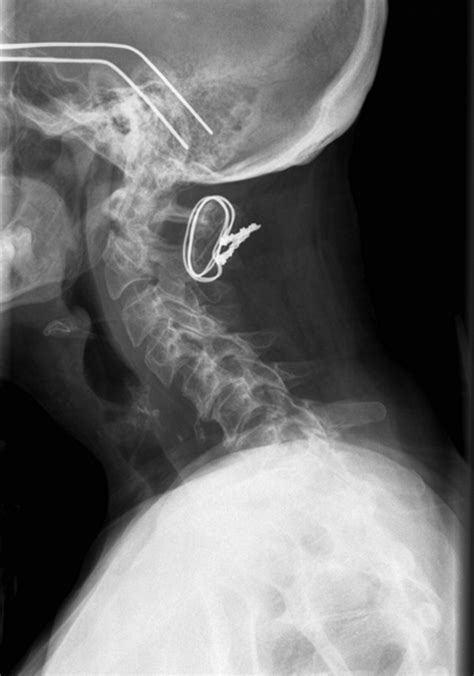

Dropped Head Syndrome (DHS) is a rare neurological condition characterized by the inability to hold the head upright, resulting in a forward flexion of the neck. This condition can significantly impact an individual's quality of life, affecting mobility, posture, and overall well-being. Understanding the causes, symptoms, and treatment options for Dropped Head Syndrome is crucial for both patients and healthcare providers.

Surgical Interventions

In severe cases, surgical interventions may be necessary. These may include:

• Cervical fusion

• Occipital-cervical fusion

• Neck brace or collar

Surgical options are typically considered when conservative treatments fail to provide adequate relief.